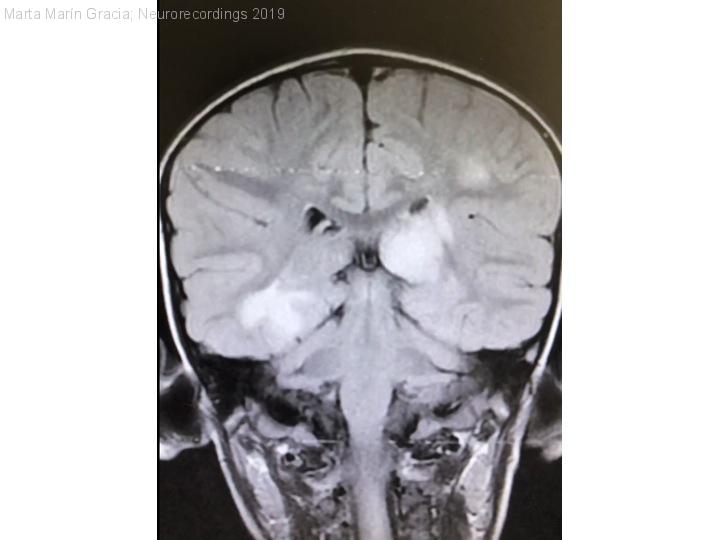

Diagnóstico final: Encefalitis aguda diseminada con anti-MOG+ asociado a Enterovirus

Varón, 4 años sin antecedentes de interés. Calendario vacunal, neurodesarrollo normales. Presenta cuadro abdominal difuso con vómitos seguido de somnolencia, mutismo y rechazo a la marcha. Ante persistencia de dolor abdominal se realizan ECO y...